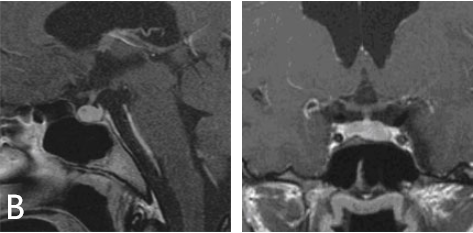

INC国际神经外科医生集团旗下组织世界神经外科顾问团(WANG)成员、世界神经外科学会联合会(WFNS)内镜委员会前主席Henry W.S. Schroeder(施罗德)教授决定采用内镜经鼻手术,成功切除了肿瘤。术后一年的核磁共振成像显示,泌乳素瘤已完全切除,垂体功能正常。内分泌检查显示泌乳素水平恢复正常,其余激素的表现也十分正常,青春之花重新绽放!

术后核磁共振成像显示肿瘤已完全切除。泌乳素水平趋于正常。垂体正常工作,无需补充激素。